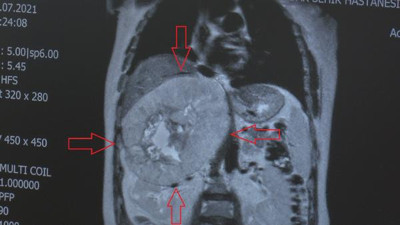

Ülkesinde birçok hastaneye gitti ama dermanı Türkiye’de buldu Ülkesinde birçok sağlık merkezine başvurmasına rağmen herhangi bir netice olamayan Sudanlı hasta dermanı Türkiye’de buldu. İştahsızlık, yorgunluk, kilo kaybı gibi şikayetleri olan 51 yaşındaki kadının vücudundan 25 santimetrelik tümör çıkarıldı.